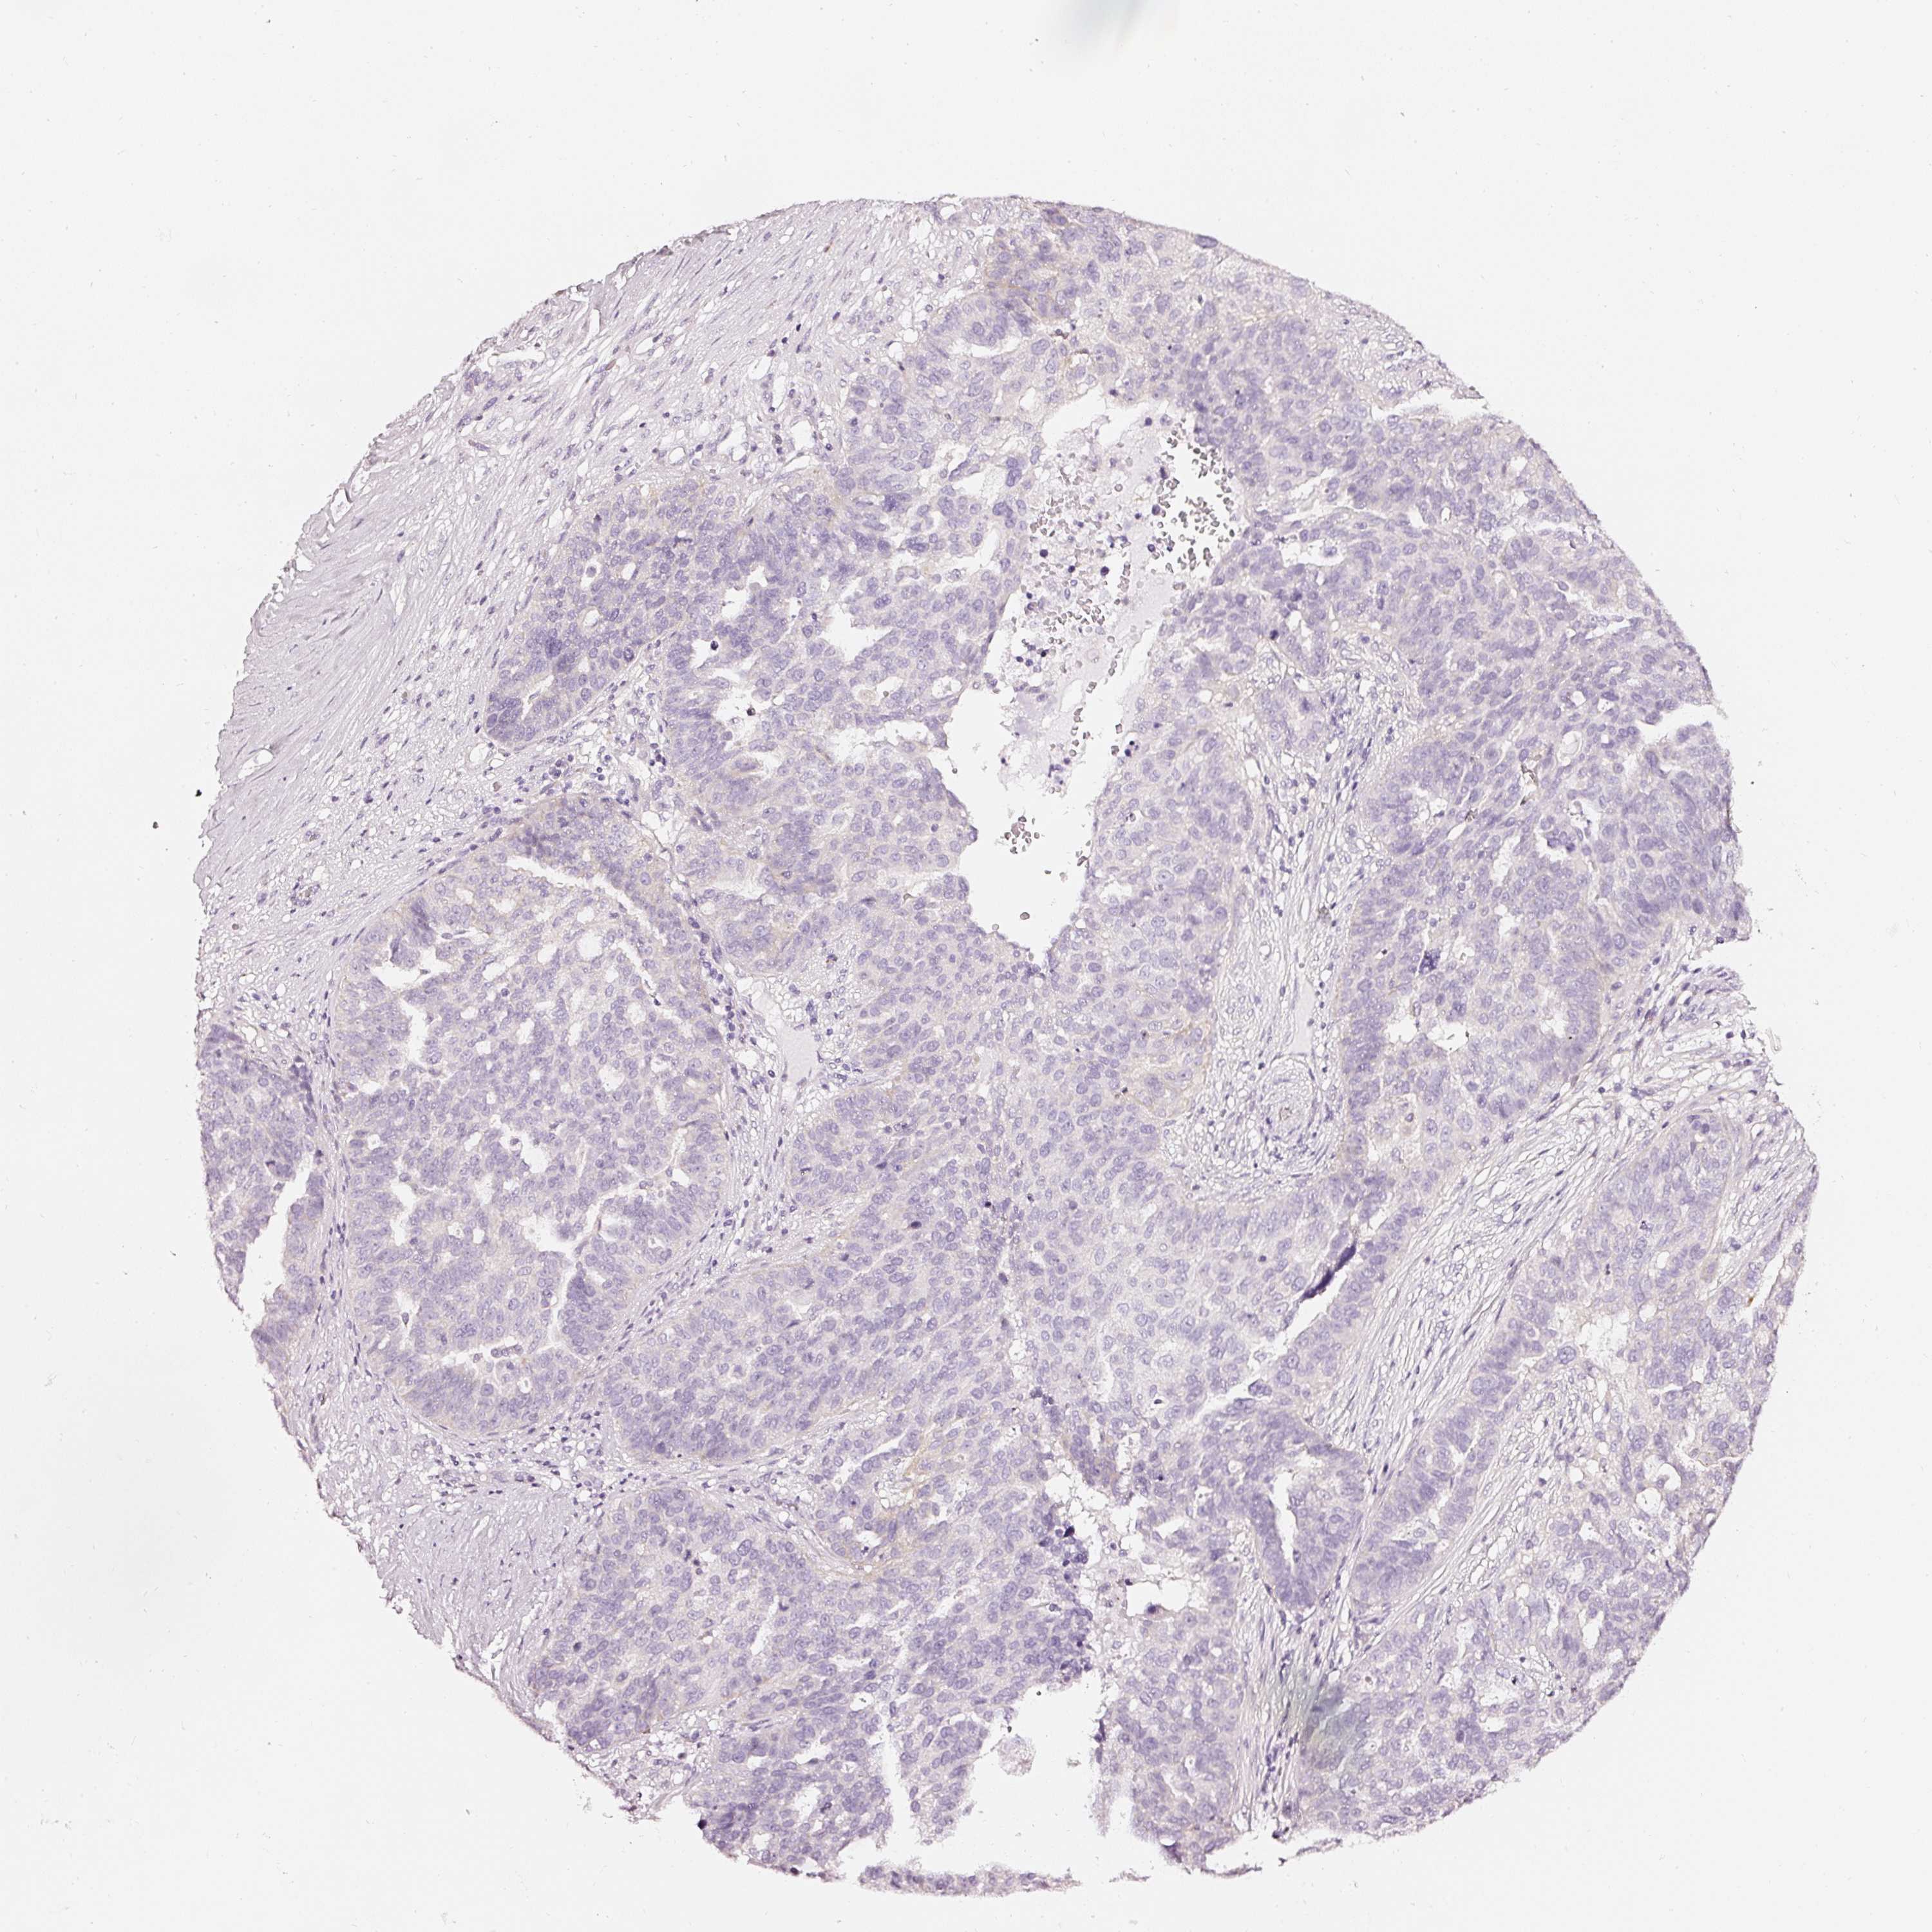

OVARIAN CANCER - Protein expressioni

A mouse-over function shows sample information and annotation data. Click on an image to view it in a full screen mode. Samples can be filtered based on level of antibody staining by selecting one or several of the following categories: high, medium, low and not detected. The assay and annotation is described here.

Note that samples used for immunohistochemistry by the Human Protein Atlas do not correspond to samples in the TCGA dataset.

Antibody stainingi

Antibody staining in the annotated cell types in the current human tissue is reported as not detected, low, medium, or high, based on conventional immunohistochemistry profiling in selected tissues. This score is based on the combination of the staining intensity and fraction of stained cells.

Each image is clickable and will lead to virtual microscopy that enables deeper exploration of all samples and also displays staining intensity scores, fraction scores and subcellular localization as well as patient and tissue information for each sample.

HPA023278

Carcinoma, endometroid